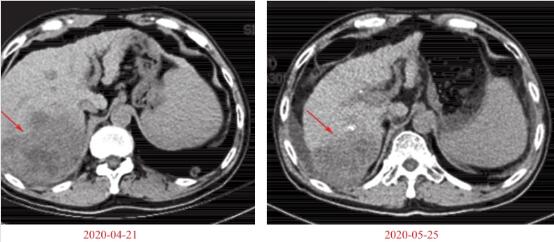

疗效评价:因仅行1个周期治疗,根据血AFP结果(61220.6μg/L,较前降低)及第2次入院前肺部CT平扫筛查结果,与前次比较示肿瘤部分消退:肝右叶病灶较前缩小(图1),双肺转移灶较前大部减小(图2),临床疗效为PR。

图1 肝脏病灶缩小

图2 多个肺部病灶缩小

1.腹部增强CT(2020-04-21,本院)

肝右叶巨大团块,最大截面8.8cm×8.5cm×10.7cm,考虑为恶性肿瘤性病变,局部累及膈肌、胸/腹壁可能,门静脉、下腔静脉及肝右静脉内瘤栓形成。肝硬化、门静脉高压,脾大,食管-胃底静脉曲张。

2.胸部平扫(2020-04-19,本院)

双肺多发结节影,转移瘤可能,较大者直径约2.1cm。